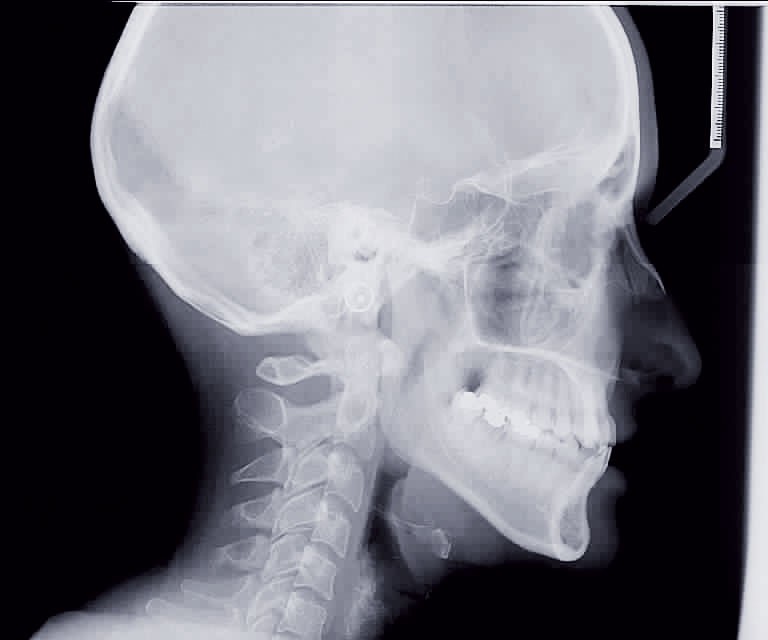

Cette patiente est venue consulter pour son occlusion inversée et ses importantes malpositions dentaires antérieures associées à la perte d’une dent et à des problèmes parodontaux.

• Malocclusion de classe III d’Angle par rétroalvéolie maxillaire,

• endoalvéolie maxillaire avec occlusion inversée antérieure et bilatérale,

• infraclusion incisive,

• fortes malpositions des incisives supérieures (dont 22 qui est en rotation axiale disto-palatine de 90°), • dysharmonie dento-dentaire (12 en « grain de riz » est aussi en rotation marginale disto-palatine de 45°),

• anomalie de la forme d’arcade maxillaire, 47, 18 et 28 sont absentes. (fig. 1 à 8), 48 est positionnée très postérieurement, quasiment au niveau de la branche montante (fig. 9 et 11).

Le sourire est inesthétique (fig. 3) et de profil il existe une rétrochéilie supérieure (fig. 2).